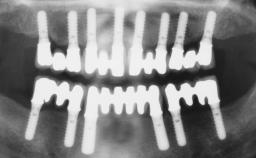

Conventional Loading of Six Implants in the Mandible and Final Restoration with a Full-Arch Metal-Ceramic FDP

# of Implants 6

Type of Implants One-Piece

Defining Characteristics Fully edentulous lower jaw to be rehabilitated with two or more implants

Modality > 4 implants, extending to mental nerve region

Bone Volume Horizontally and vertically sufficient

Defining Characteristics Fully edentulous lower jaw to be rehabilitated with an implant-borne fixed dental prosthesis

Retention Screw-retained, with 4 or more splinted implants Screw-retained, with 4 or more splinted implants